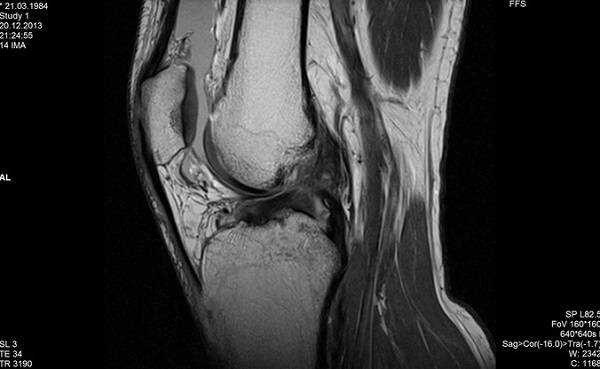

МРТ коленного сустава, разрыв передней крестообразной связки